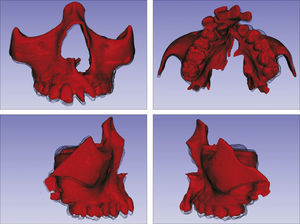

O surgimento e o aumento da acessibilidade da TCFC agregaram uma maior credibilidade ao diagnóstico clínico e às investigações científicas no estudo das deformidades craniofaciais19. Todavia, as informações 3D fornecidas pelas TCFC ainda vêm sendo rotineiramente analisadas de forma 2D, por medidas lineares em cortes ortogonais5,20. A construção e sobreposição de modelos virtuais 3D ainda é uma metodologia pouco difundida. Este estudo é um dos pioneiros que utiliza este método para avaliação de ERM em pacientes com fenda. A sobreposição baseia‐se na construção dos modelos virtuais 3D, utilizando o software SLICER21, pelos arquivos obtidos na TCFC, seguida pela sua justaposição, que utiliza a base do crânio como referência e a final obtenção dos métodos de medidas intitulados: sobreposição por semitransparência e mapa por códigos de cores22. A sobreposição por semitransparência revela uma análise qualitativa, em que o momento pós‐tratamento é retratado por uma malha preta translúcida, sobre o modelo inicial em vermelho (figs. 9 e 10). O aparelho em leque demonstrou um deslocamento de quase todos os dentes para vestibular e uma movimentação vestíbulo‐posterior do segmento menor (lado esquerdo [fig. 9]). O mapa por códigos de cores permite um complemento da análise visual, sendo que cada cor reflete uma alteração na posição das estruturas: azul – recuo; verde – estabilidade e vermelho – expansão. A intensidade da cor está diretamente relacionada à quantidade de movimentação. Todo o mapa é seguido por uma escala, com os valores em milímetros para cada cor (figs. 11 e 12). A observação feita na sobreposição por semitransparência do expansor em leque é confirmada no mapa por código de cores e nas medidas lineares. Uma menor porção de vermelho é visualizada em molares, quando comparada aos pré‐molares. O deslocamento para posterior e vestibular do menor segmento é constatado pela presença de azul na mesial dos dentes e vermelho nas eminências alveolares do lado em questão. Diferentes tonalidades de azul são vistas na cervical dos incisivos, possivelmente uma retroinclinação em decorrência da ausência de apoio mecânico no local. Para a quantificação das mudanças no posicionamento dentário, primeiramente identificou‐se, nos 3 cortes ortogonais, os pontos de referência para a medida (ponta da cúspide mésio vestibular dos primeiros molares superiores e ponta da cúspide dos caninos), tanto do lado direito como do lado esquerdo, utilizando o software ITK Snap23. Os pontos foram marcados com uma esfera de 0,5mm de diâmetro, identificando a posição 3D destas referências no espaço (fig. 13). A aferição das distâncias Euclidianas entre as esferas foi realizada com o auxílio da ferramenta Q3DC no programa SLICER23. O paciente A obteve um aumento de 3mm na distância intercanina e de 6mm na distância intermolar. Na elucidação do paciente que utilizou o disjuntor mini‐Hyrax invertido com BTP (B), observa‐se na sobreposição por semitransparência um deslocamento vestibular, principalmente dos pré‐molares e uma constância das demais áreas, achados corroborados no mapa por código de cores. A área que não está verde é a região de pré‐molares, vermelho por vestibular e azul por palatino, notando uma tonalidade entre verde e vermelho (amarelo) no corpo da maxila do lado menor (esquerdo). A oclusal dos molares, em vermelho, representa a erupção dos elementos.

Sobreposição com semitransparência dos modelos 3D do tratamento com o aparelho em leque. Antes da expansão representado por vermelho e após a expansão pela malha fina translúcida. Observa‐se um trespasse da malha preta para vestibular em molares, pré‐molares e canino, indicando que houve expansão em toda essa região.